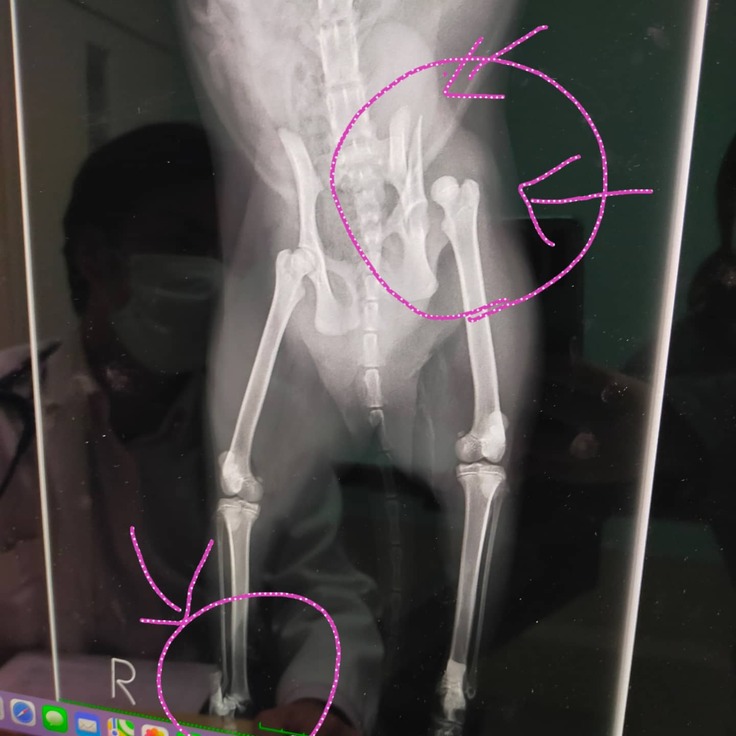

11/3夜、交通事故直後と思われる野良猫を保護しました。病院の診断で生後半年くらいの女の子、骨盤骨折、脱臼、両足の骨折がわかりました。

奇跡的に内蔵は無事で、垂れ流していますが、排泄も自分で出来ています。現在家で名前を『きなこ』と名付け保護していますが立てない状況です。病院の説明では一度の手術では完治は無理とのことでした。それに何度か手術をして骨を治してもちゃんと歩けるようになるかわからないと…。

逆にそのまま安静にしてれば骨は自然にくっついてそれなりに立てるようになるかもしれないと。一度の手術でもとても高額で最低30万〜プラス検査、投薬その後の通院にお金がかかるということでした。お恥ずかしい話ですが、私にはその資金を出すことができない状況です。すごく悩んでどこかでお金を借りるか?募金箱を置く?クラウドファンディング?と、この文章を考え、書いて、申請し、訂正し、その間に土日が入り…そんなことをしているうちに日にちは経ち、交通事故から10日経ってしまいました。 本日、病院に行き診断書等お願いしたところ…もう骨はくっつき始めてるから手術は出来ませんと言われました。

骨が飛び出そうなところもあり縫合していただいて、自宅療養中です。それでもこれから通院は必要で、本来ここで手術費用のご支援をお願いするつもりでしたが、これからの治療費用をお願いしたいと思います。

骨折している猫『きなこ』の治療費用にひ使わせて頂きます。